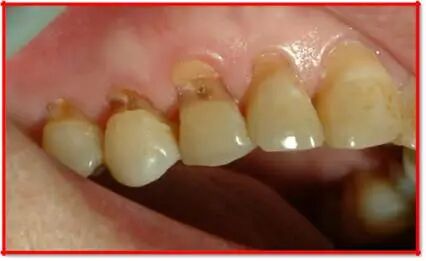

男,40 岁,牙齿常常酸痛。他的楔状缺损是由于不正确的涮牙方法引起的,其楔状缺损较浅,没有涉及牙髓,可以通过充填方法治疗。